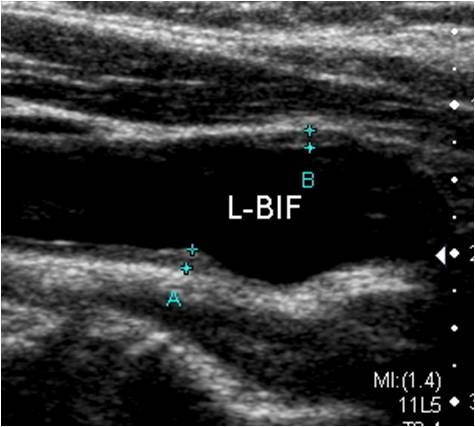

경동맥 초음파 검사는 동맥경화의 초기 단계를 확인할 수 있습니다. 혈관벽이 두꺼워지는 ‘내중막 두께(IMT, Intima-Media Thickness)’를 측정하여, 향후 심혈관계 질환 위험도를 예측합니다. IMT가 0.9mm 이상이면 동맥경화 진행이 의심되며, 1.5mm 이상이면 플라크 형성이 진행된 것으로 봅니다.

경동맥 초음파 검사는 준비 과정이 간단합니다. 공복 상태일 필요가 없으며, 목 주변의 금속 액세서리나 목도리만 제거하면 됩니다. 검사 시간은 약 10~20분 정도이며, 환자는 눕거나 고개를 약간 돌린 상태로 검사를 진행합니다. 탐촉자를 목 부위에 대고 초음파를 투사하면 화면에 경동맥의 단면이 실시간으로 나타나며, 의사는 혈류 속도와 벽의 상태를 분석합니다. 혈관이 막혀 있거나 좁아진 부분에서는 혈류 속도가 비정상적으로 증가하므로, 이를 통해 협착의 정도를 정량화할 수 있습니다.

검사 결과는 일반적으로 다음과 같이 구분됩니다.

- 정상: 혈관 내벽이 매끄럽고, 내중막 두께(IMT)가 0.8mm 이하

- 경미한 변화: IMT 0.9~1.2mm

- 중등도 동맥경화: IMT 1.3~1.5mm

- 플라크 존재 또는 중증 협착: IMT 1.5mm 이상